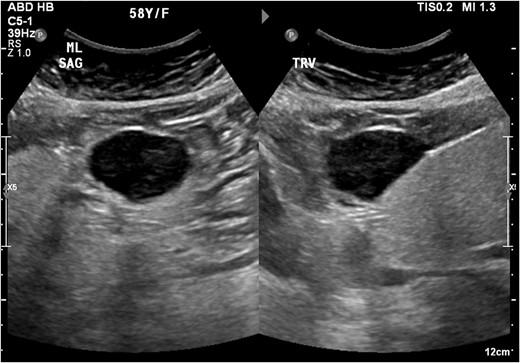

An ultrasound of the abdomen revealed a homogonous hypoechoic lesion anterior to the left hepatic lobe (Fig. 1). Color doppler images (not shown) shows internal blood flow. A subsequent abdominal computed tomography (CT) scan was done, and it revealed a 4.9 × 5.5 cm well-defined, homogeneous, progressively enhancing mass anterior to the left hepatic lobe (Fig. 2). The differential diagnoses included desmoid tumor, leiomyoma, hemangioma and gastrointestinal stromal tumor (GIST). EGD and CT colonography were done and both came back negative for synchronous lesion.

Homogonous hypoechoic lesion anterior to the left hepatic lobe. Color doppler images (not shown) shows internal blood flow.